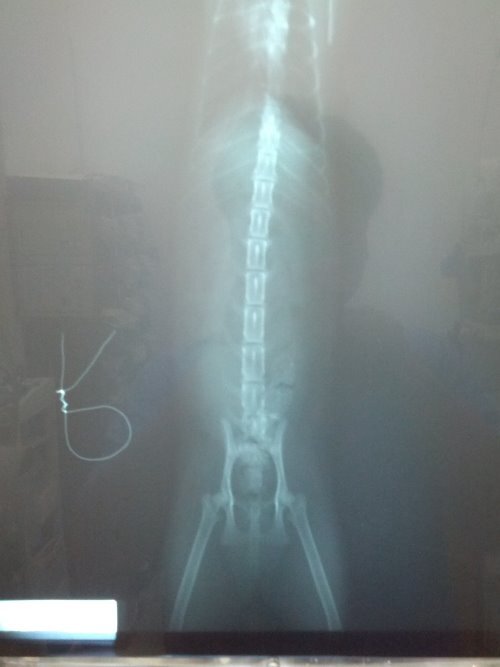

主題: 下半身癱瘓~求助 申請者姓名: Jason Yang 花色: 申請日期: 2013-06-07 00:05:28 申請者部落格: 申請者臉書網址: 所在縣市/合作醫院: 新北市/哲生動物醫院 治療費用: 6200元 需求人數: 8人 已結案 (2013-08-06 14:01:08) 報名人員: Chloe Liang(已付款)、alicelin(已付款)、Sean Chun-hsiang Yo、貓球球(已付款)、himawari(已付款)、himawari、himawari、Bei Yi Su(已付款)、Fei Lika Tsai(已付款)、Fu Nk(已付款)、Yvonne Chen(已付款)、 候補人員: 動物病情說明: 在我的工廠發現一隻玩到下半身不能動的貓,於晚上九點多發現,已詢問淡水之上哲動物醫院該如何處置~目前餵食罐與與放置鐵籠~已鋪設毛毯及紙箱~~明日將帶前往醫院檢查是否有救...

貓目前意識清楚~唯有腳~尾巴無法動作

貓咪檢查後發現第一薦椎骨折,造成後半身癱瘓,眼睛也有病變,經過六天治療,貓咪都不願意自己進食,精神很差,每天醫師都有幫他擠尿按摩腹部幫助他排便,治療不見改善,幾經考量,為減輕貓咪的痛苦,只好以人道的方式送貓咪一程,還請各位幫忙貓咪。謝謝!